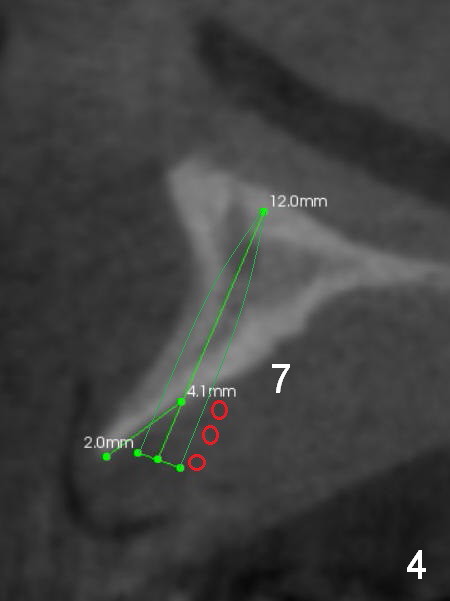

A 69-year-old man would consider implant option for his upper front teeth (Fig.1: #5-9) if there is no separate bone graft procedure. He does not want implants for his lower left molars (#18,19), since he has had a partial denture. In fact the bone at #5-9 is so thin that 2-3 mm 1-piece implants can be placed at #5,7 and 9 (Fig.2-5 (CT coronal sections (B: buccal)) for a 5-unit bridge (Fig.1). To support and increase the longevity of the latter, implants at #18,19 are mandatory (Fig.6,7).

Wheel saws will be used to split the ridge before drilling at #7 (Fig.4). Surgical bur is to be used for ridge reduction prior to osteotomy at #19 (Fig.6), while at #18, osteotomy depth will be 10 mm for 8 mm implant (Fig.7).